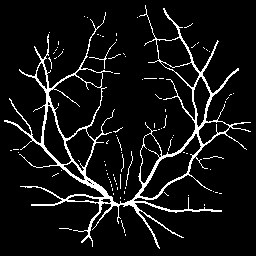

Synthetic Data Samples

Figure: Synthetic data generated by StyleGAN2-ADA for ACDC (top) and FIVES (bottom) datasets. Left to right: first 3 are original images, next 3 generated using 5% real data, last 3 using 10% real data.